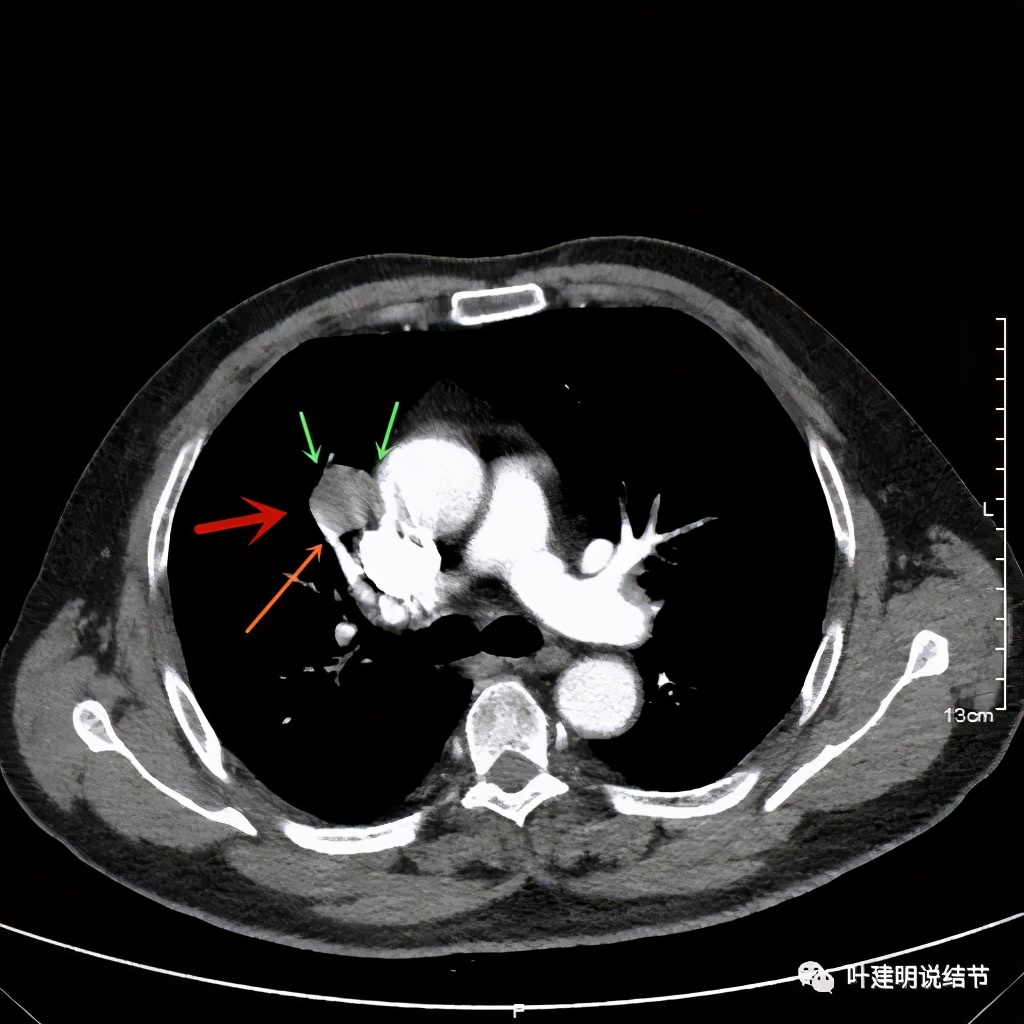

可见右上叶占位,我们现在知道了结果以后回头看,发现病灶的边缘在各个层面都是过于光滑(绿色箭头所示)。血管紧贴病灶边走行(桔色箭头所指),是不是有侵犯看不清楚,若是靶扫描加重建可能会更清楚点。支气管感觉也是贴着病灶走,但有的层面是不是截断,也不看的不太清楚。有的层面见局部有点状高密度(蓝色箭头所指),是不是错构瘤的局部钙化呢?若是纵隔窗又是如何?

上图示病灶边缘过于光滑(绿色);局部有点状钙化(蓝色)

上图示病灶边缘过于光滑(绿色);血管贴边(桔色);

上图示病灶边缘过于光滑(绿色);血管贴边走行(桔色)

以上几图也示病灶边缘过光(绿色);血管贴边,感觉没受侵犯(桔色)

事前来看,达2.4厘米的不均质实性肿块,增强有轻度不均匀强化,血管贴边走行,支气管疑有截断,恶性不能除外,而且可能性较大。但现在经过手术已已经证实是错构瘤的情况下,我们回头来看,其实有许多不符合恶性的地方: